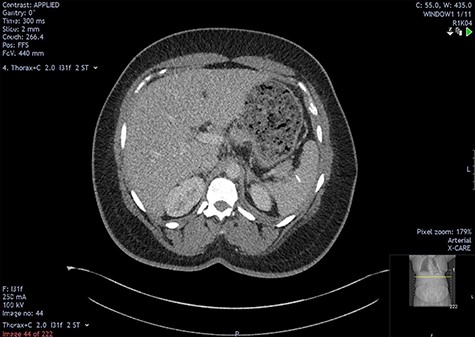

The initial bloods showed haemoglobin 121 g/l, white cell count 29.2x109/l, lactate 0.8 mmol/l, C-reactive protein 348 mmol/l and deranged alkaline phosphatase at 175 mmol/l, with other blood results in normal ranges. A diagnosis of intra-abdominal sepsis secondary to acute cholecystitis was suspected and initial resuscitation was commenced. A computerized tomography (CT) scan of the thorax, abdomen and pelvis demonstrated a mild left pleural effusion with bibasal subsegmental consolidation, splenic subcapsular haematoma, splenic hypodensity and a linear hyperdensity density crossing the upper anterior pole of the spleen, referred to hereafter as the foreign body (Figs 1–3).

Two-mm axial section from the outpatient CT scan performed in November 2021, demonstrating resolution of the perisplenic haematoma with foreign body in situ.